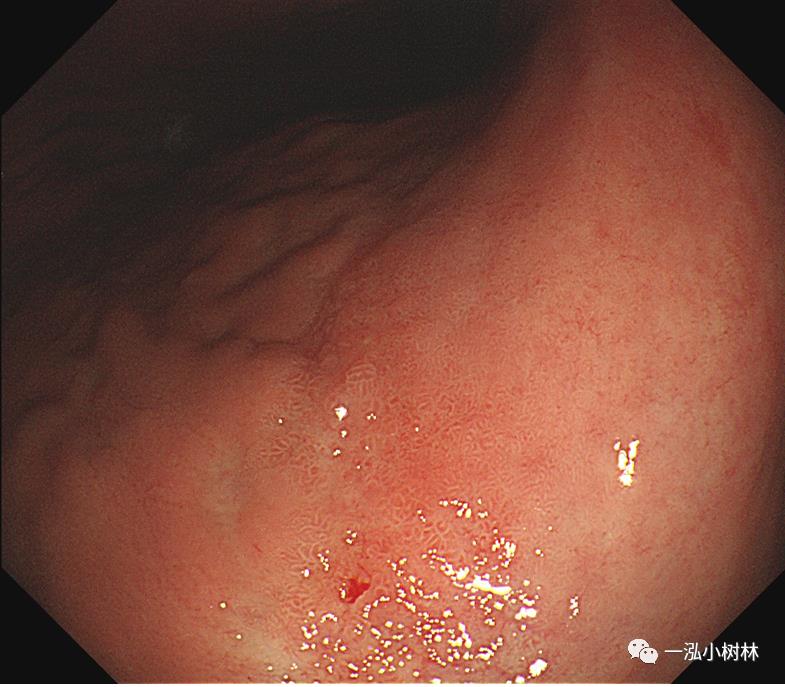

图4a 白光内镜:胃体下部高分化腺癌(Tub1)

图4b 白光内镜:胃体下部高分化腺癌(Tub1)